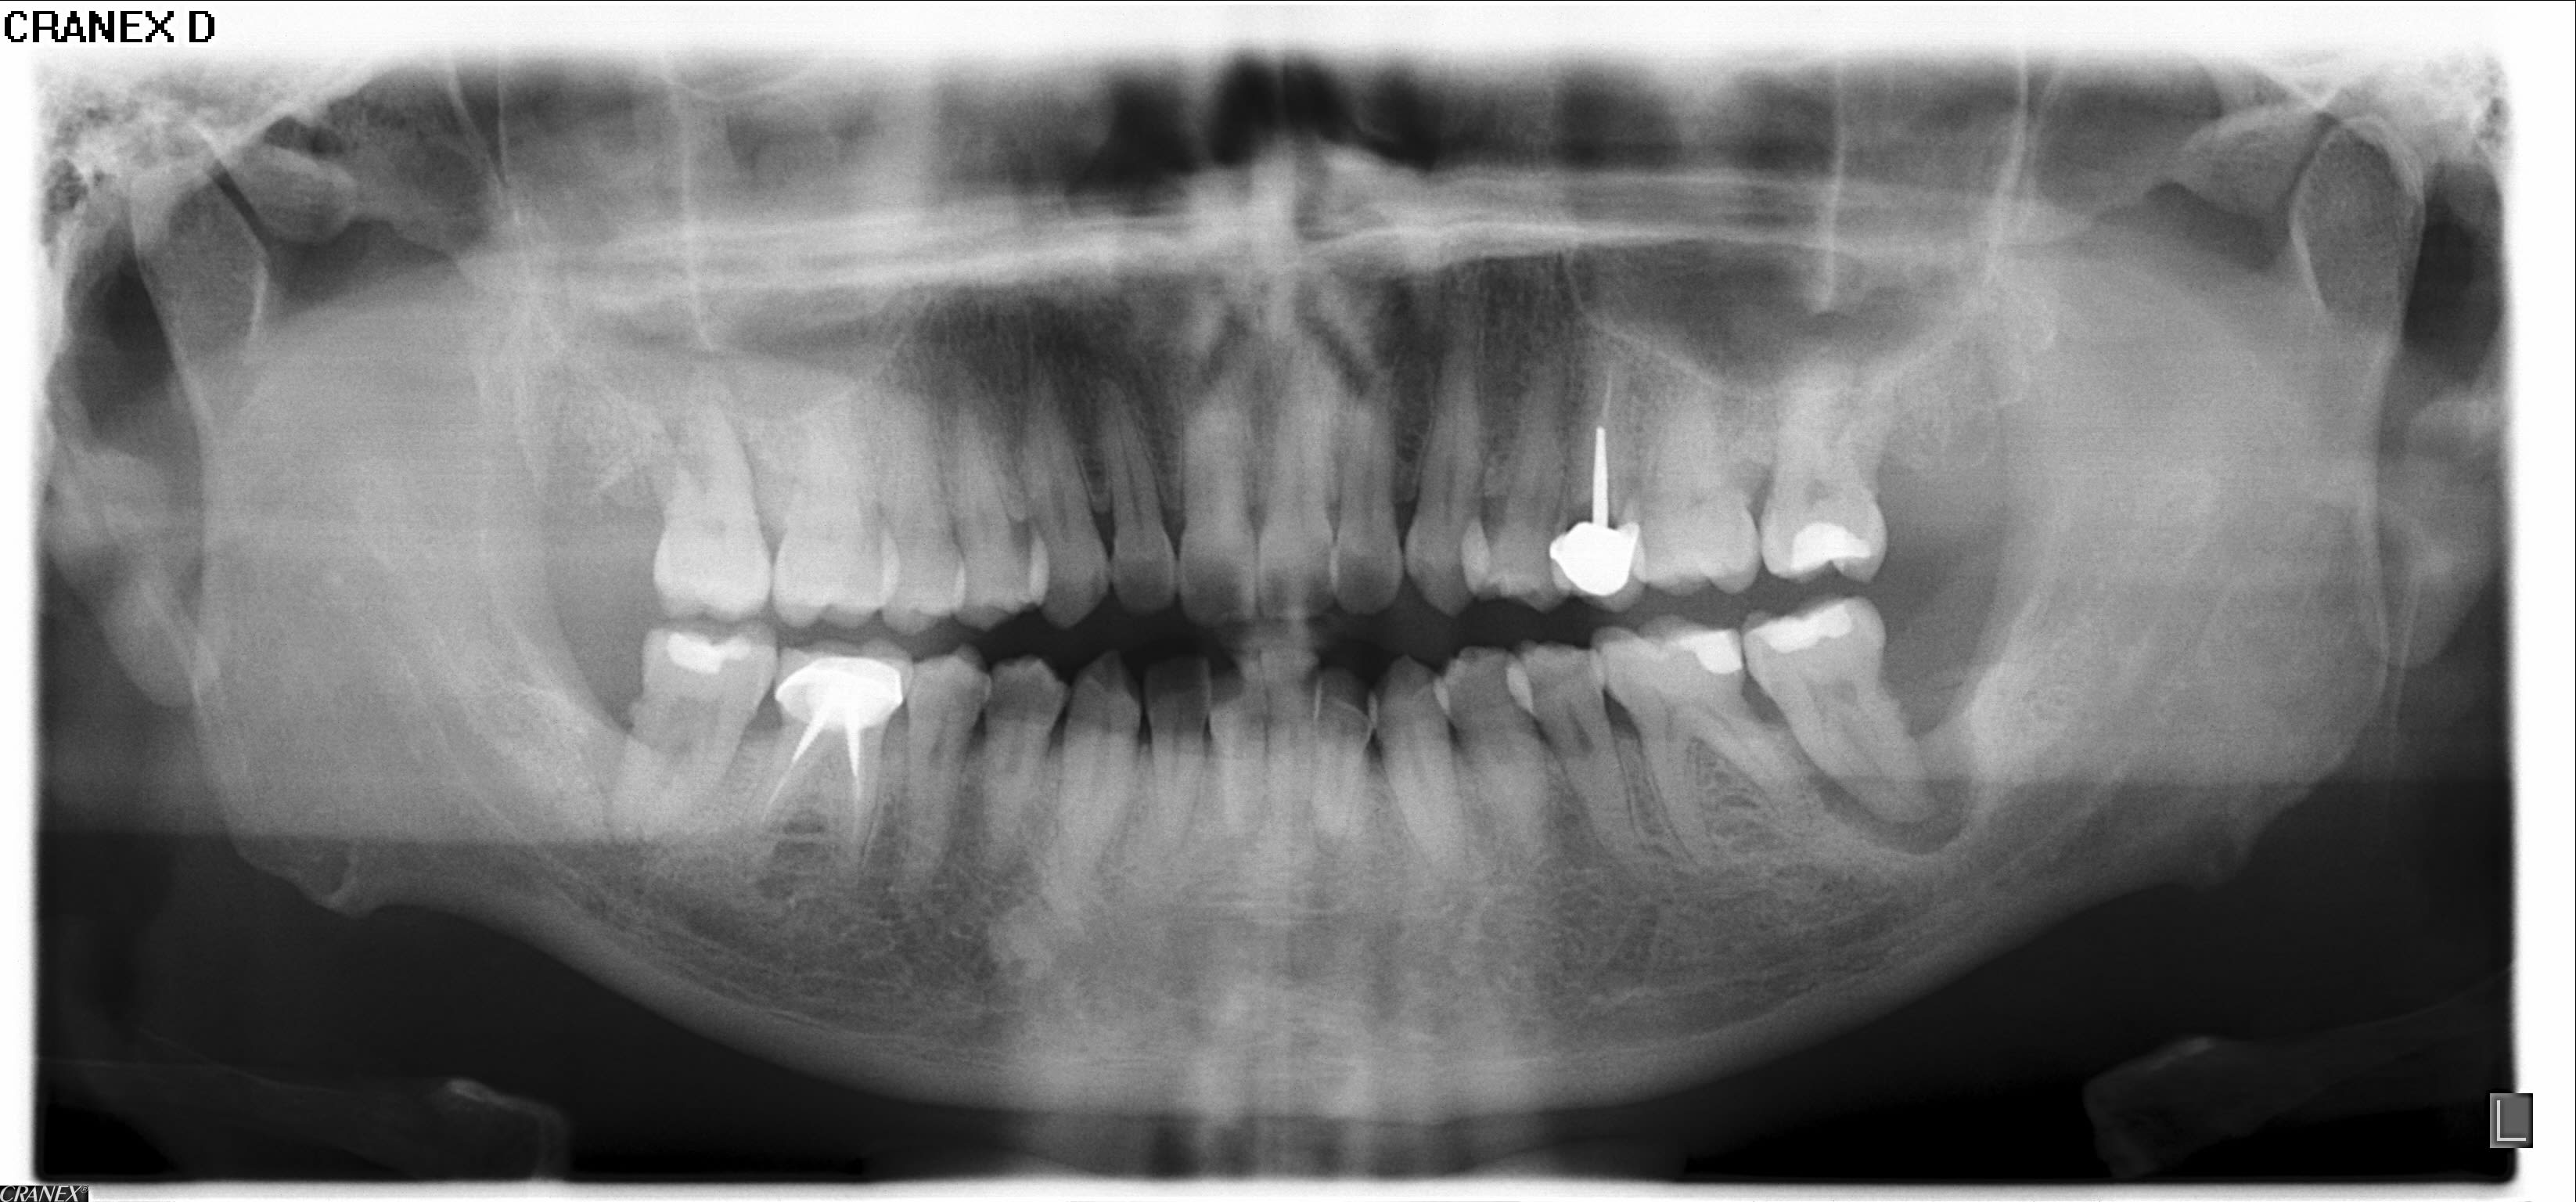

Ci joint la pano d'un patient la cinquantaine.

Concernant la 37 (mobilité III), tenteriez vous l'endo + surfaçage ou avulsion d'emblée car c'est perdu d'avance ?

hormis le fait que l'image peut evoquer une fracture

je constate qu'il n'y a , curiseusement pas de lesion interradiculaire

Si on regarde la pano, il y a de l'os en Ml, c'est donc une énorme lésion péri-apicale qui a du être aggravée par le contexte occlusale... de là à la sauver...

personne ne l'a observé, mais ce site n'est pas implantable en l'état après extraction ; ce qui justifie plus encore l'intere t de conserver cette dent : c'est le seul moyen naturel d'assurer une regenrération osseuse en cas de guérison